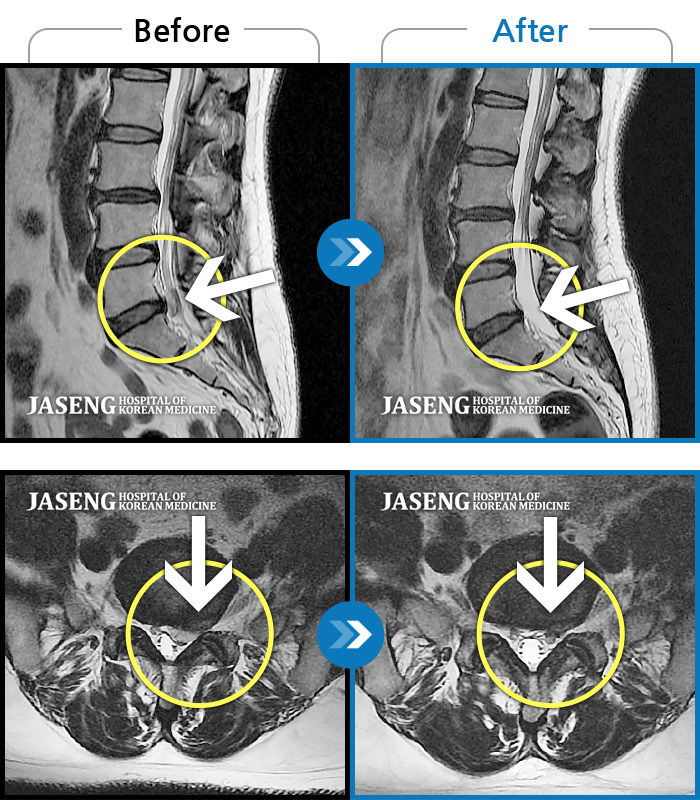

Before

After

환자에게 사전 동의를 받아 동일 조건에서 촬영되었습니다.

개인에 따라 치료 후 부작용이 발생할 수 있으니 의료진과 상담 후 치료를 진행하시기 바랍니다.